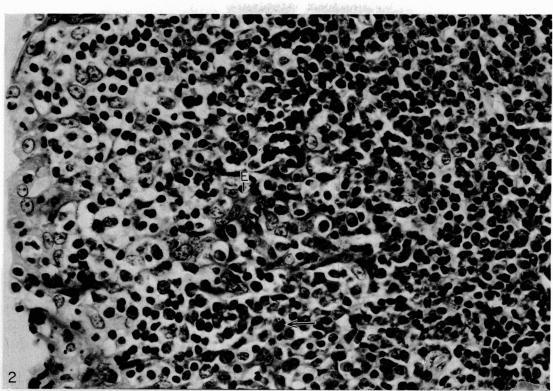

通过免疫组织化学显示的人扁桃体中含免疫球蛋白的细胞。

Immunoglobulin-containing cells in human tonsils as demonstrated by immunohistochemistry.

Intracellular immunoglobulin has been demonstrated in human palatine tonsils by the unlabelled antibody peroxidase-antiperoxidase complex (PAP) method in which rabbit antiserum to a range of human immunoglobulins (Igs) was linked to the PAP complex by an intermediate stage of swine antiserum to rabbit Ig. The effects of different methods of fixation and processing have been compared, formol-saline fixation giving the best results. The PAP technique proved greatly superior to the fluorescein isothiocyanate (FITC)-based technique, not only in sensitivity but in permitting study of the finer histological and cytological features. The lymphoid follicles are shown to have three distinct zones, two forming the follicle centre (zones (a) and (b)), and the third (zone (c)) the lymphocyte cap. Ig synthesis appeared to begin in the cells in zone (b). IgG, IgA, IgM, IgE and IgD were present in all tonsils, with IgG predominating, confirming that the tonsil resembles lymph nodes more closely than it does alimentary lymphoid tissue. Some follicles contained more than one type of Ig. The tonsil appears to have a well-developed T-dependent area, the lymphoid follicles forming a B-cell area. The structure of the tonsil would seem to facilitate contact between its lymphoid tissue and antigens in the crypts, and it is postulated that some T cells within the crypt epithelium, after contact with antigen, may leave the tonsil by the efferent lymphatics and enter the peripheral circulation by the thoracic duct, whilst other primed T cells interact with B cells in the follicle centres. Some B cells may then start to synthesize immunoglobulin, whilst others become memory cells in the lymphocyte 'cap' of the follicle.

运用未标记抗体过氧化物酶-抗过氧化物酶复合物(PAP)法在人腭扁桃体中证实了细胞内免疫球蛋白的存在。该方法中,一系列针对人免疫球蛋白(Ig)的兔抗血清通过猪抗兔Ig血清这一中间阶段与PAP复合物相连。比较了不同固定和处理方法的效果,结果显示甲醛生理盐水固定效果最佳。PAP技术被证明在灵敏度上以及在对更精细的组织学和细胞学特征的研究方面都大大优于基于异硫氰酸荧光素(FITC)的技术。淋巴滤泡显示有三个不同区域,两个构成滤泡中心(区域(a)和(b)),第三个(区域(c))是淋巴细胞帽。Ig合成似乎始于区域(b)的细胞。所有扁桃体中均存在IgG、IgA、IgM、IgE和IgD,其中IgG占主导,这证实扁桃体与淋巴结的相似性高于与消化道淋巴组织的相似性。一些滤泡含有不止一种类型的Ig。扁桃体似乎有一个发育良好的T细胞依赖区,淋巴滤泡构成B细胞区。扁桃体的结构似乎便于其淋巴组织与隐窝中的抗原接触,据推测,隐窝上皮内的一些T细胞在与抗原接触后,可能通过输出淋巴管离开扁桃体,并经胸导管进入外周循环,而其他致敏T细胞则在滤泡中心与B细胞相互作用。然后一些B细胞可能开始合成免疫球蛋白,而其他B细胞则在滤泡的淋巴细胞“帽”中成为记忆细胞。